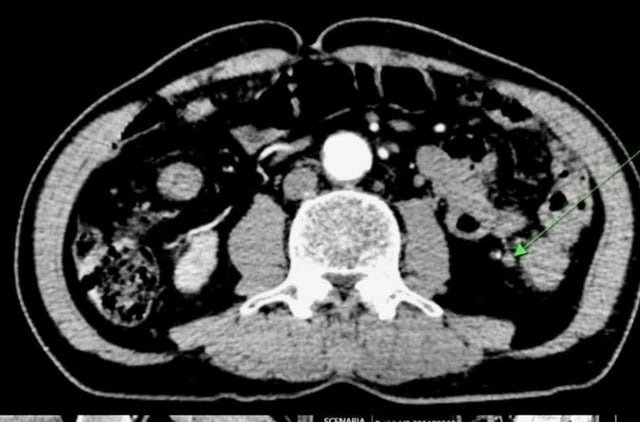

Đau bụng quanh rốn, đi khám phát hiện mắc hai loại ung thư

Sống khỏe - 14/10/2025 20:23

Nam bệnh nhân 62 tuổi ở Quảng Ninh được phát hiện mắc cùng lúc ung thư thực quản và đại tràng sigma, may mắn điều...